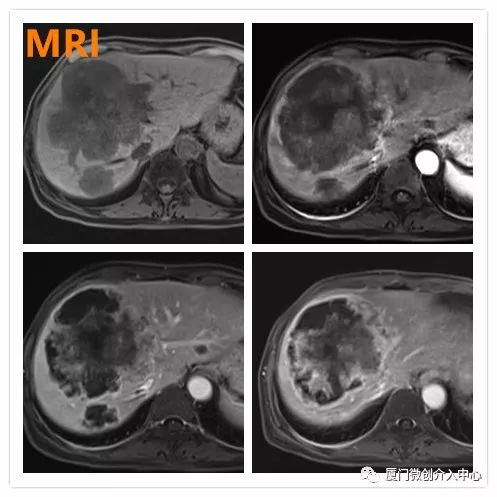

老年女性患者,诊断为乙状结肠腺癌并肝多发转移。肝脏肿瘤病灶巨大且多发,针对肝脏转移瘤行载药微球栓塞治疗,肠道肿瘤行动脉化疗灌注治疗。

肝动脉化疗栓塞+肠系膜上动脉化疗灌注治疗

术后1月复查提示肝转移瘤病灶内部明显坏死,肿瘤缩小

肠道肿瘤标志物明显下降(CEA 术前:3493 ng/mL,术后:196.3 ng/mL;CA19-9 术前:895.8 U/mL,术后:110.1 U/mL),病灶控制理想。